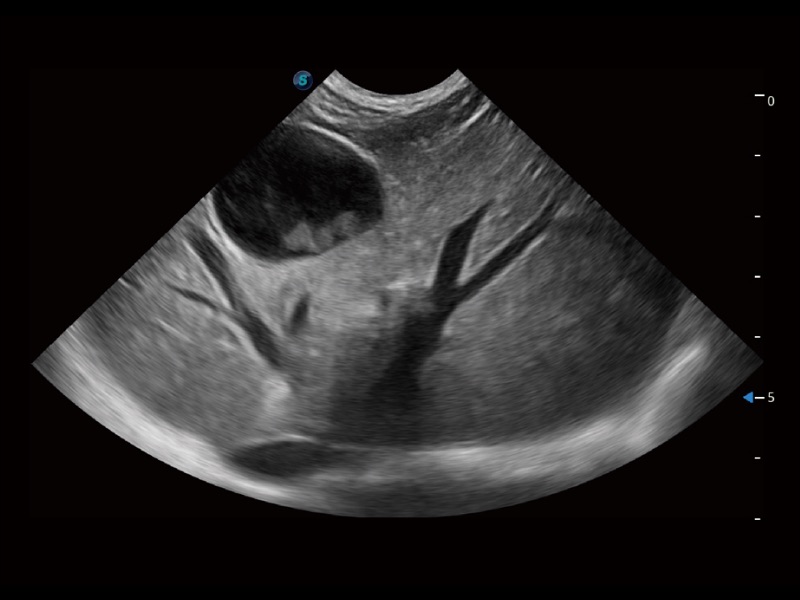

动物是人类最亲密的朋友和最值得信赖的伙伴。百老汇电子游戏官网也一直致力于探索动物专用的超声影像解决方案。全新推出的ProPet系列,是百老汇电子游戏官网在动物超声影像智能化、专业化、精准化的一次跨越式革新。动物不能用言语来表述自己的不适,通过超声影像,ProPet系列搭建了动物医生与不同物种沟通的“桥梁”,为动物医生注入了“治愈之力”。 ProPet 70将是您值得信赖的超声伙伴。它配备了复合材料线阵探头,帮助动物医生获得卓越精准的临床图像。同时ProPet 70直观便捷的操作体验以及专业的测量工具,可为不同体型和生理结构的动物带来全面临床评估,切实为动物医生提供智能、专业、精准的超声影像解决方案。

ProPet 70 进一步提升了微米成像算法,更加注重对基础原始图像的还原和保留,在有效减少斑点噪声、增强组织边界显示的同时,避免过度优化丟失真实的解剖信息。

ProPet 70专为动物医生设计,对不同的动物体型和生理结构作出了针对性的优化。通过动物影像专用软件,可满足个性化的应用需求,帮助动物医生获得更精确的诊断数据。

ProPet 70 全新的动物超声智能软件和丰富的探头群,为动物医生提供了高清晰度和精细分辨率的图像,无论在宠物、马科、畜牧还是实验室动物等应用中都可以轻松应对,为您的日常工作带来满意的体验。